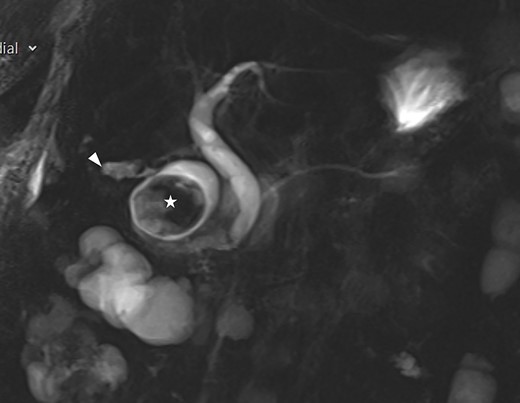

A frail 83-year-old female attended the emergency department with epigastric pain, vomiting and signs of sepsis with a heart rate of 101 and a temperature of 38°C. She had a recent admission with severe cholecystitis that was managed conservatively with intravenous antibiotics. On examination, she had tenderness in the right upper quadrant. Blood revealed an acute kidney injury, a CRP of 189 with normal liver function tests. Axial imaging demonstrated aerobilia with a dilated common bile duct of 14 mm and there was a 3.5 cm stone impacted in the first part of duodenum with evidence of a cholecysto-duodenal fistula (Figs 1–3).

MRI scan showing the gallbladder adherent to the duodenum with an impacted stone in the duodenum.